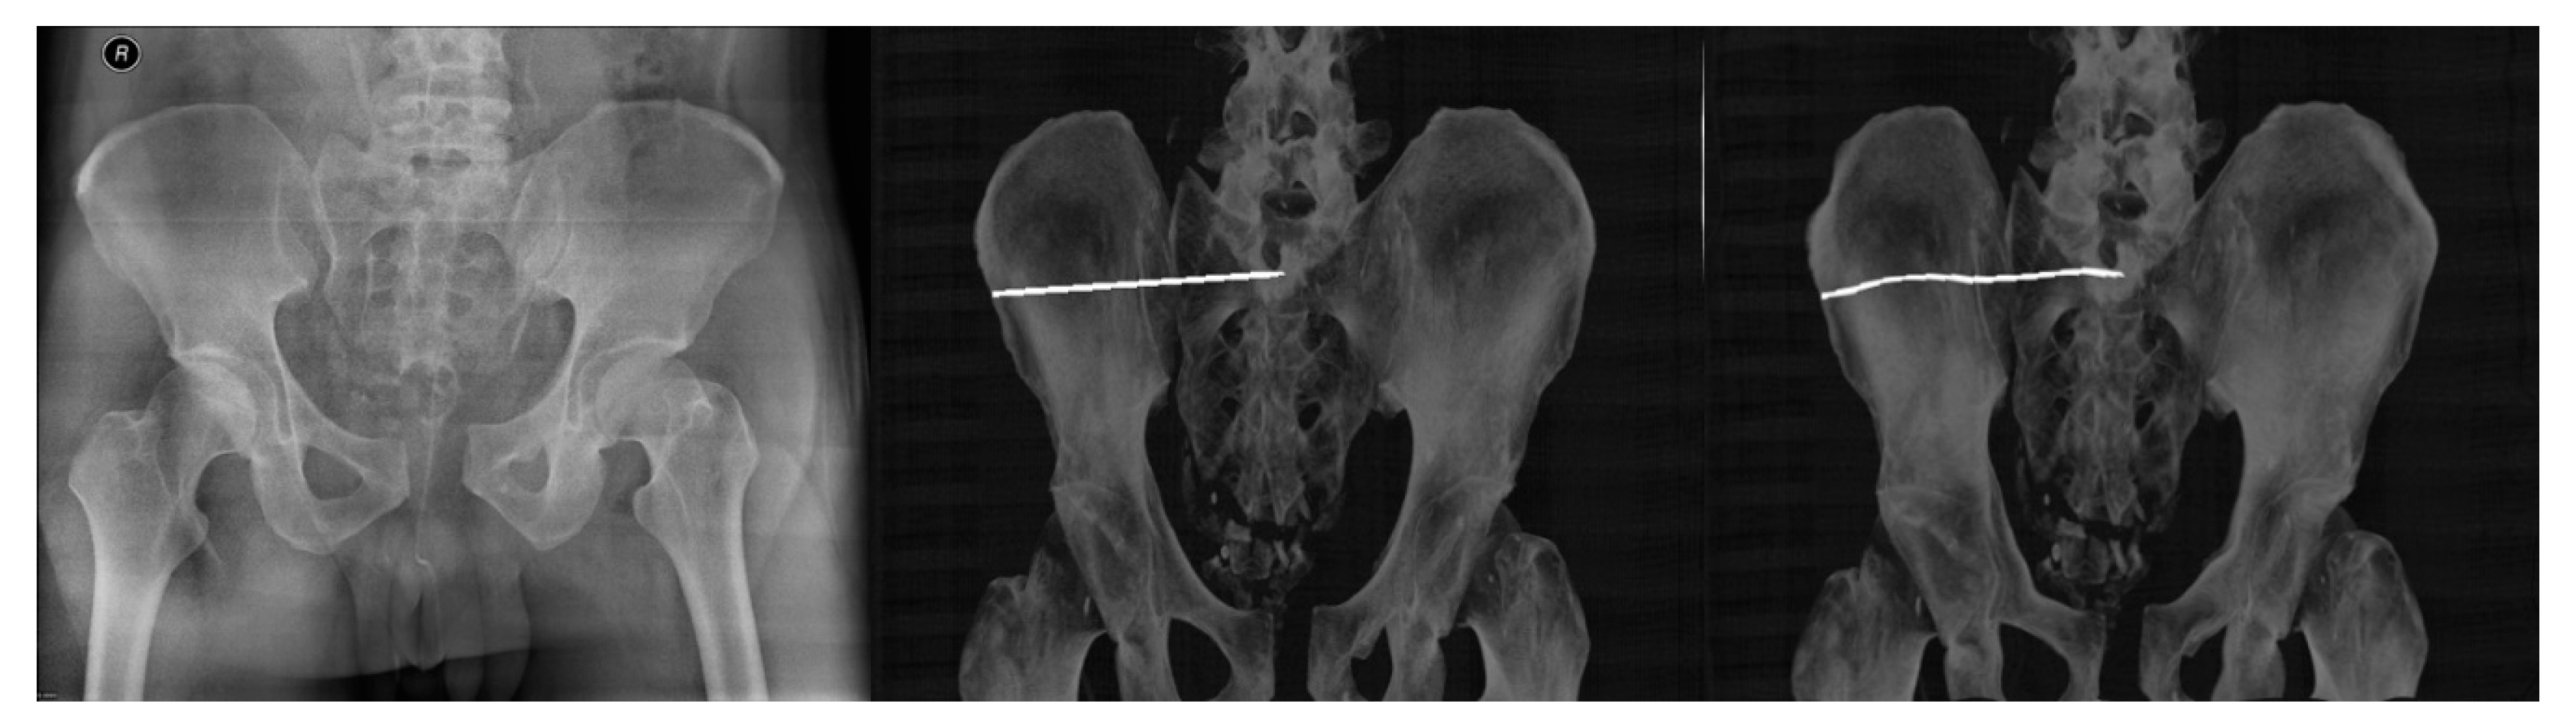

- Multimodal image registration of DRR projections to a reference X-ray image

- Multimodal (X-ray/CT) image registration for optimal CT slice selection according to the reference X-ray image.